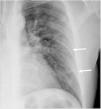

El primer sistema de cuantificación (6A) consiste en dividir cada pulmón en tres campos: superior, medio e inferior (fig. 1). Según esta división, la extensión de las opacidades pulmonares se clasifica como leve si se afecta un solo campo, moderada si hay opacidades en 2-3 campos pulmonares, y grave si hay más de 3 campos afectados.

Radiografía de tórax posteroanterior que muestra la división en 6 campos pulmonares (sistemas de cuantificación 6A y 6B) mediante dos líneas horizontales: campo pulmonar superior (de vértices a margen inferior del botón aórtico), medio (margen inferior de botón aórtico a tercio medio de borde cardíaco) e inferior (tercio medio de borde cardíaco a senos costofrénicos).